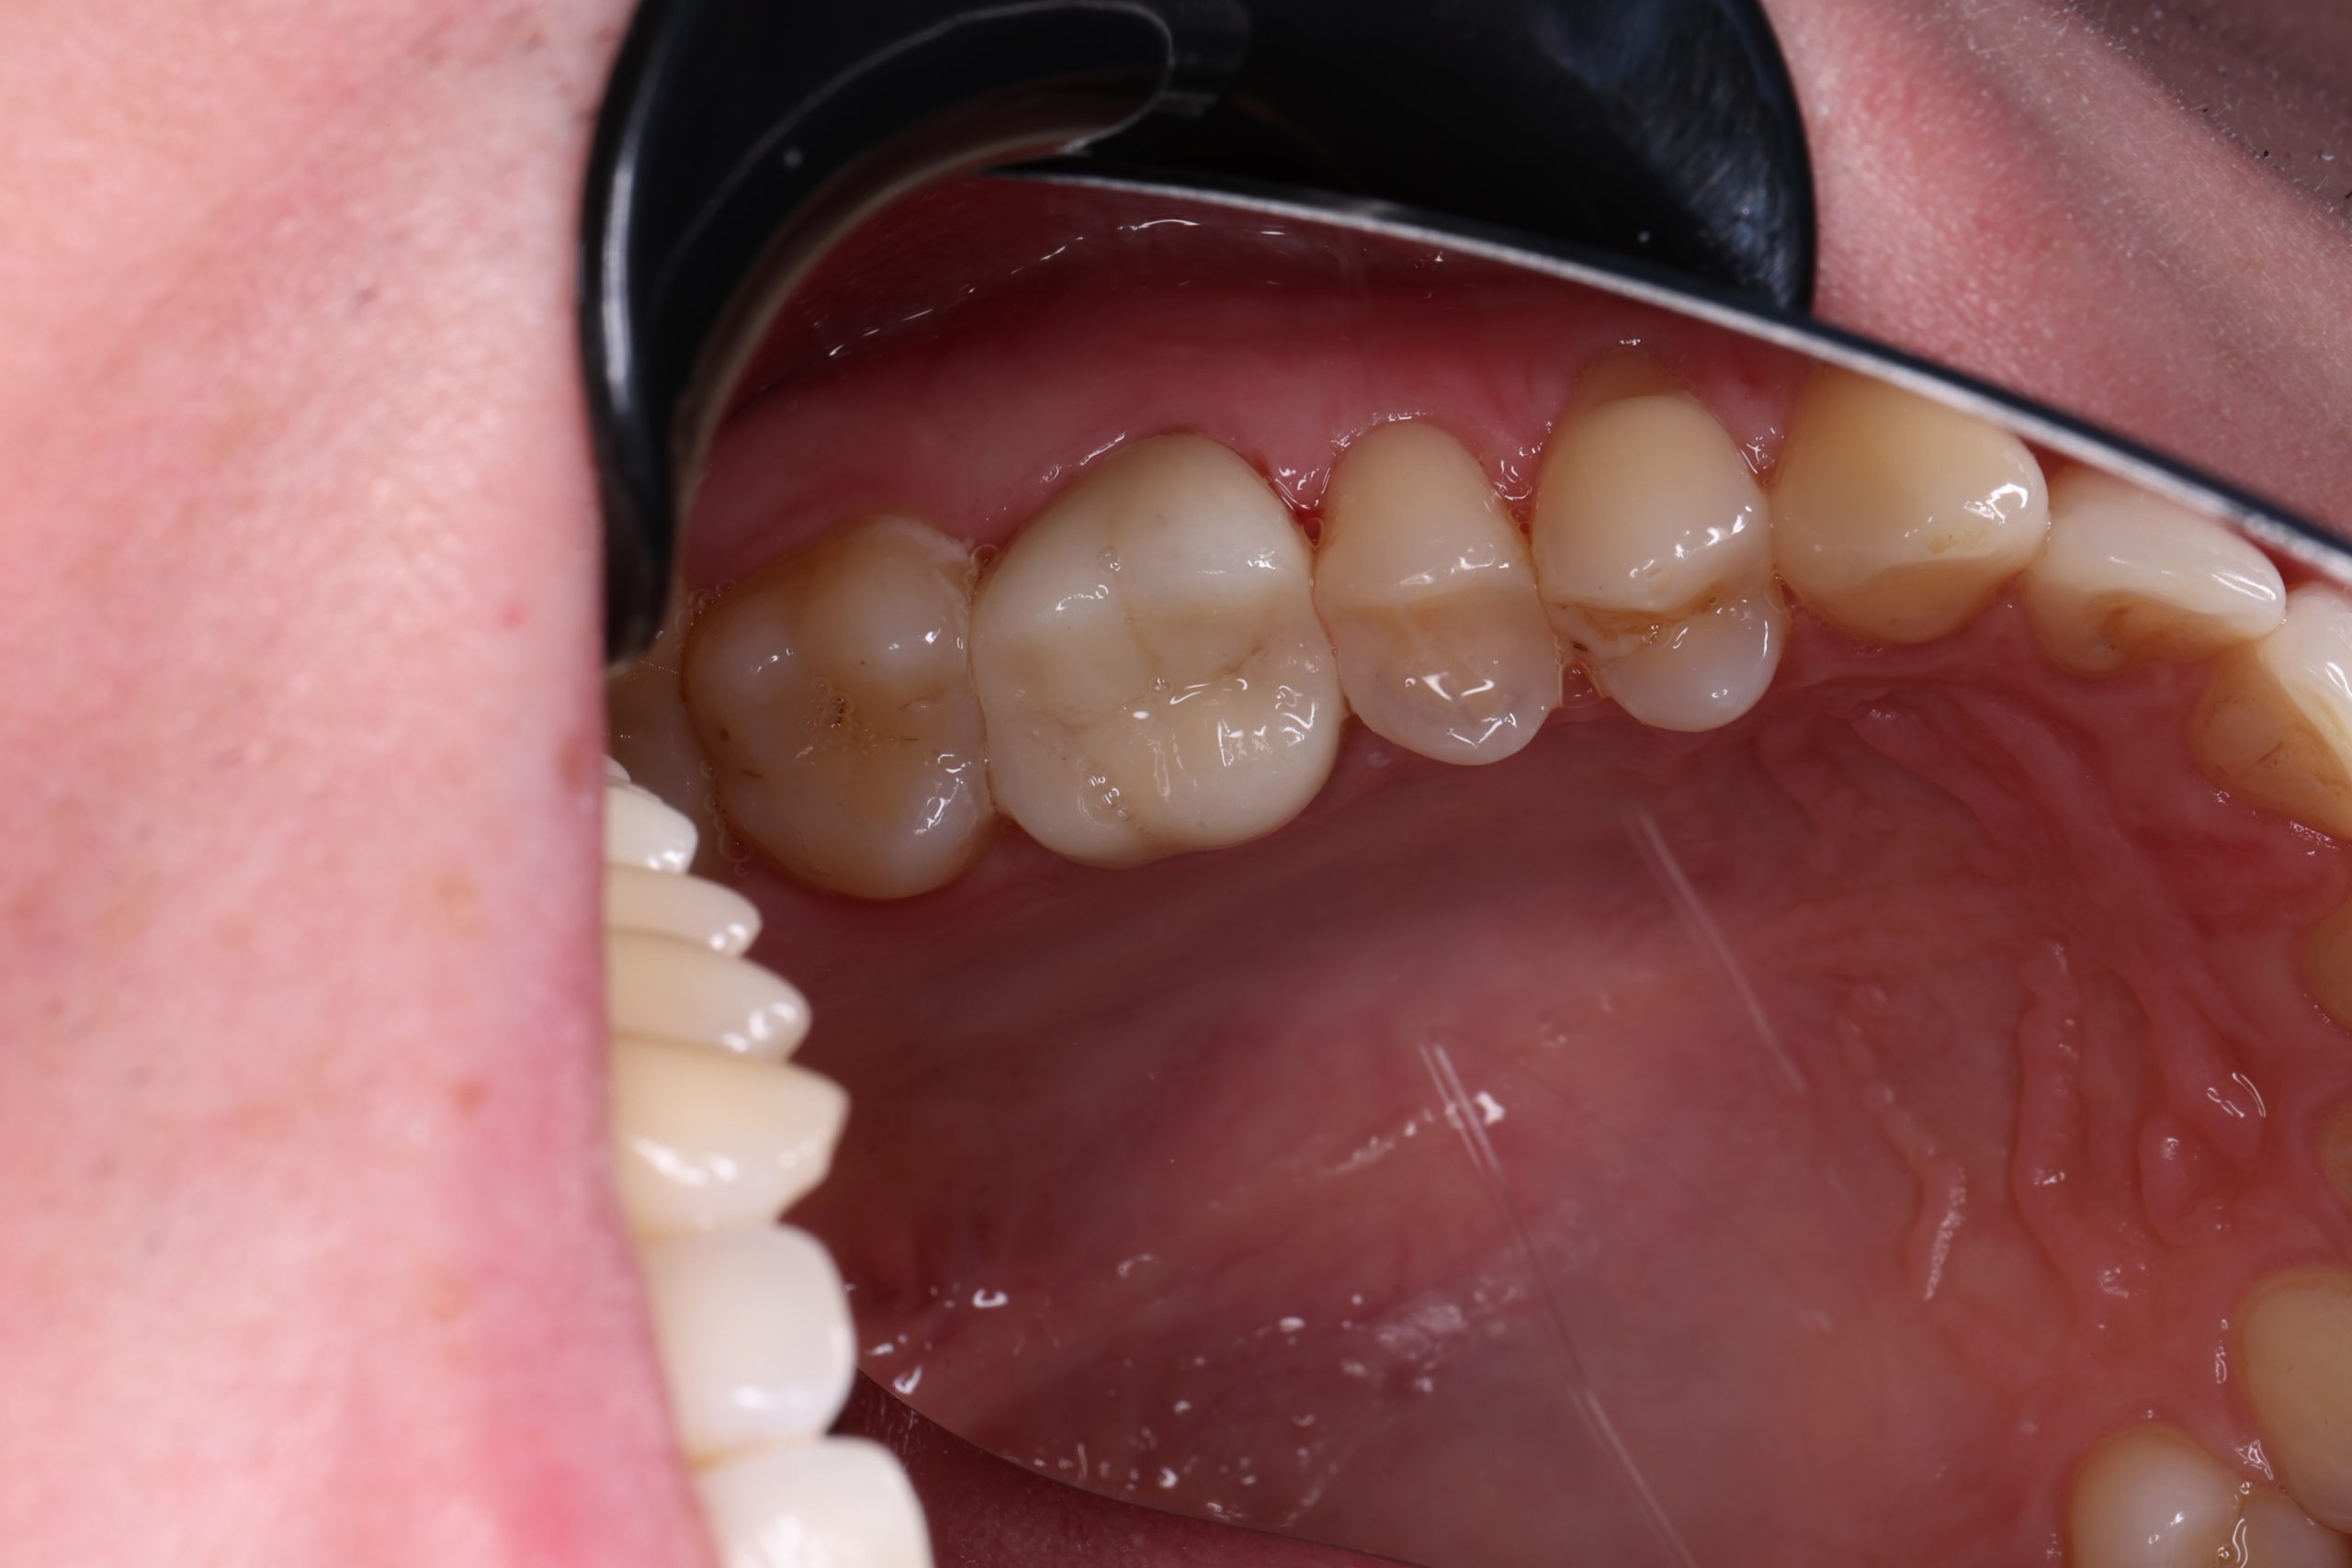

Inside every tooth lies a narrow chamber that contains nerves and blood vessels — the dental pulp. When deep decay, a leaking filling, or trauma allows bacteria to reach this inner space, the pulp becomes inflamed and then infected. The result is pressure, sensitivity, and often an unmistakable throbbing pain.

Under bright magnified light, a tiny opening is created and every canal located — even the hidden ones that often cause failures elsewhere. - Cleaning and shaping